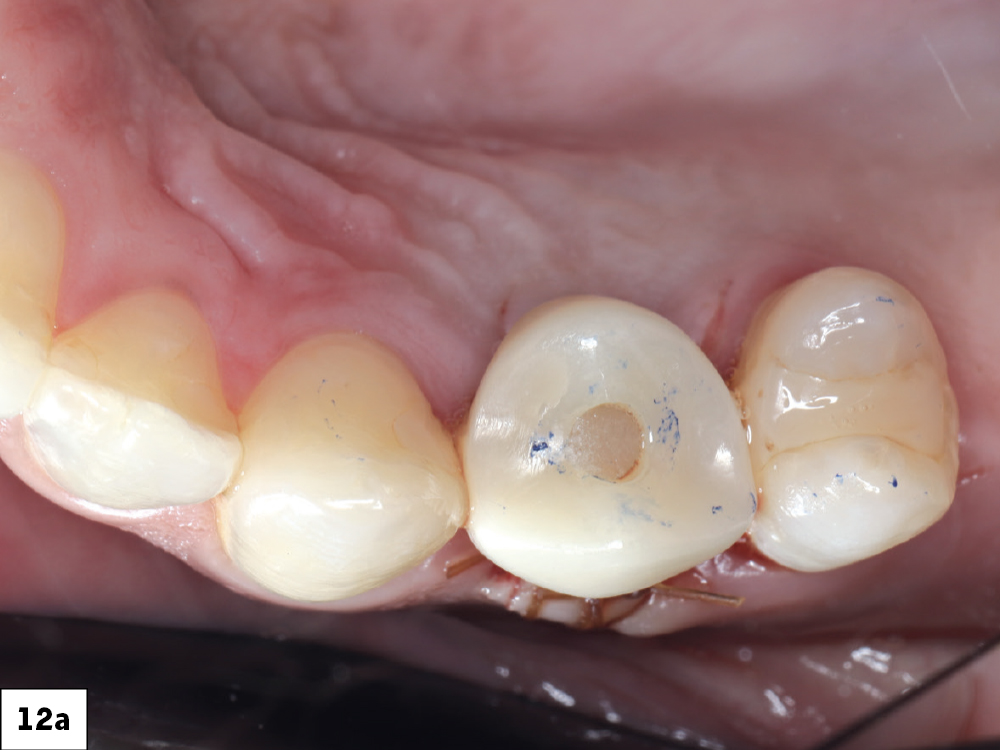

Each screw-retained crown was seated onto the corresponding Glidewell HT Implant, torqued to the manufacturer’s specifications, and sealed with PTFE tape and composite resin

Figures 12a, 12b: Each screw-retained crown was seated onto the corresponding Glidewell HT Implant, torqued to the manufacturer’s specifications, and sealed with PTFE tape and composite resin. Occlusal contacts required only minor adjustments. Occlusion was relieved in the design phase to promote undisturbed osseointegration and eliminate premature loading. The fit was passive, the emergence contours harmonious, and the esthetic integration excellent.